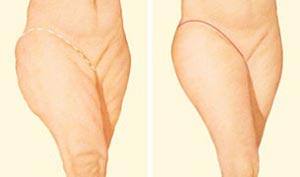

لاغر و کوچک کردن دائمی ران با لیپوساکشن و جراحی لیفت

برای لاغر و کوچک کردن ران لازم است که پوست و چربیهای اضافهی موجود در قسمت داخلی و خارجی ران برداشته شوند. این کار معمولاً بعد از جراحی لاغری ران و یا در مورد افرادی انجام میشود که علی رغم ورزش کردن و گرفتن رژیم غذایی نمیتوانند چربیهای اضافه ناحیه بالای ران را از بین ببرند. اگر شما وزنی متعادل دارید و نسبت به داشتن سبک زندگی سالم (غذای مناسب و داشتن فعالیت فیزیکی کافی) متعهد هستید، انجام روشهای لاغر کردن ران میتواند به شما کمک کند که فرم زیبای ران پاهای خود را بازیابید و آنها را به شکل مورد انتظار خود دربیاورید.

در این روش میتوان با استخراج چربیهای اضافهی موضعی، رانها را لاغرتر کرد و به آن فرم زیباتری بخشید. بسیار مهم است که متخصصی که لیپوساکشن را انجام میدهد، در انجام این کار مهارت داشته و نتایجی طبیعی ایجاد کند. وجود فضای کوچکی بین قسمت بالایی و پایینی ران به لحاظ زیبایی ظاهری بسیار خوشایند و مناسب است اما وجود تفاوت زیاد بین این دو ناحیه، ظاهری غیرطبیعی و ناسالم دارد و کاملاً مشخص است که در این ناحیه جراحی انجام شده است. هیچ کس قطعاً به دنبال داشتن چنین ظاهری نیست. در صورتی که جراح شما در انجام لیپوساکشن این ناحیه تبحر و تجربه نداشته باشد، عدم هماهنگی و تعادل بین قسمتهای بالایی و داخلی ران با دیگر قسمتهای ران میتواند شدید و ناخوشایند باشد.

جراحی لیفت ران

جراحی لیفت ران شامل مراحل زیر میشود:

- نتایج: بلافاصله پس از جراحی، هموار بودن و لاغری رانها قابل مشاهده است اما نتایج نهایی جراحی بعد از گذراندن دوره بهبودی و با برطرف شدن تورم و کبودی رانها، مشخص خواهند شد.

برش لیفت داخلی ران

در این روش، برشها در داخل کشاله ران ایجاد میشوند و به سمت پایین ادامه پیدا کرده و تا پشت رانها میروند. در تکنیک دیگری برای لیفت داخلی ران، برش از کشاله ران تا زانو امتداد پیدا میکند. ممکن است با توجه به شرایط خاصی که دارید نیز متقاضی انجام برش جزئی لیفت داخلی ران باشید که در این صورت، تنها برشی در ناحیه داخلی کشاله ران ایجاد میشود. جراح شما پس از ارزیابی شرایط و خواستههای شما به شما خواهد گفت که کدام تکنیک برش برای شما مناسبتر است.

برش لیفت خارجی ران

برای بهبود فرم خارجی رانها لازم است که برشی در قسمت خارجی کشاله ران ایجاد شود که این برش دورتا دور لگن و سپس کمر امتداد پیدا میکند. در تکنیکهای پیشرفتهتر برش، جراح سعی میکند که برشها را در محلهایی ایجاد کند که تا جای ممکن توسط انواع لباسها پوشیده میشود. اما در هر صورت ممکن است این برشها گسترده باشند.